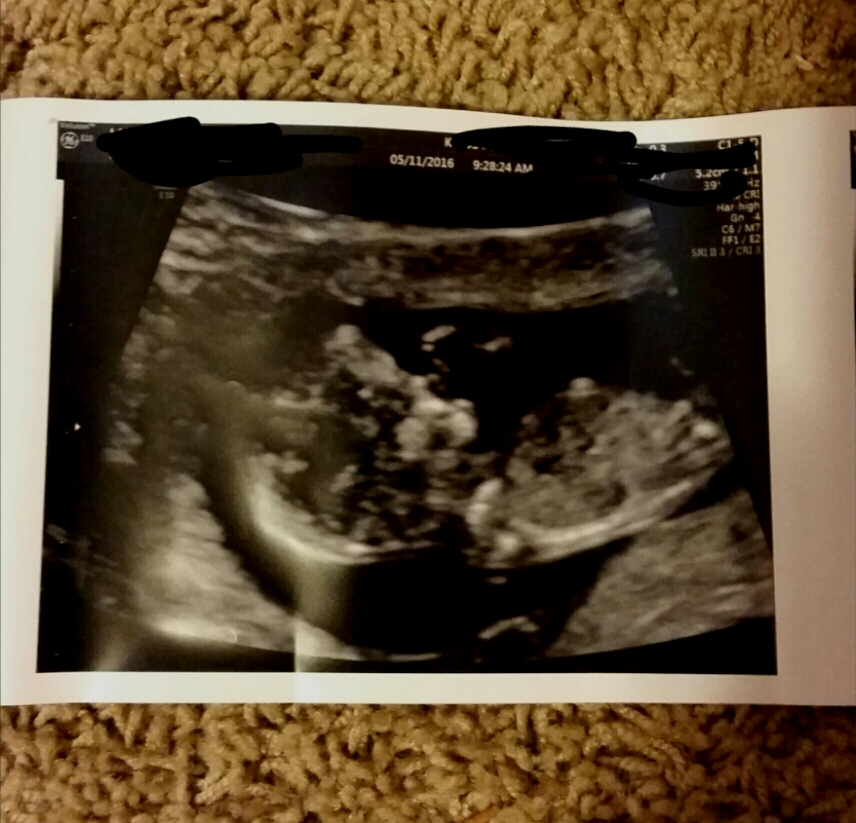

Scan is TODAY! Any last guesses for me?! 4th and last baby!

Dr says girl!!!!!!!

Attachment 31646